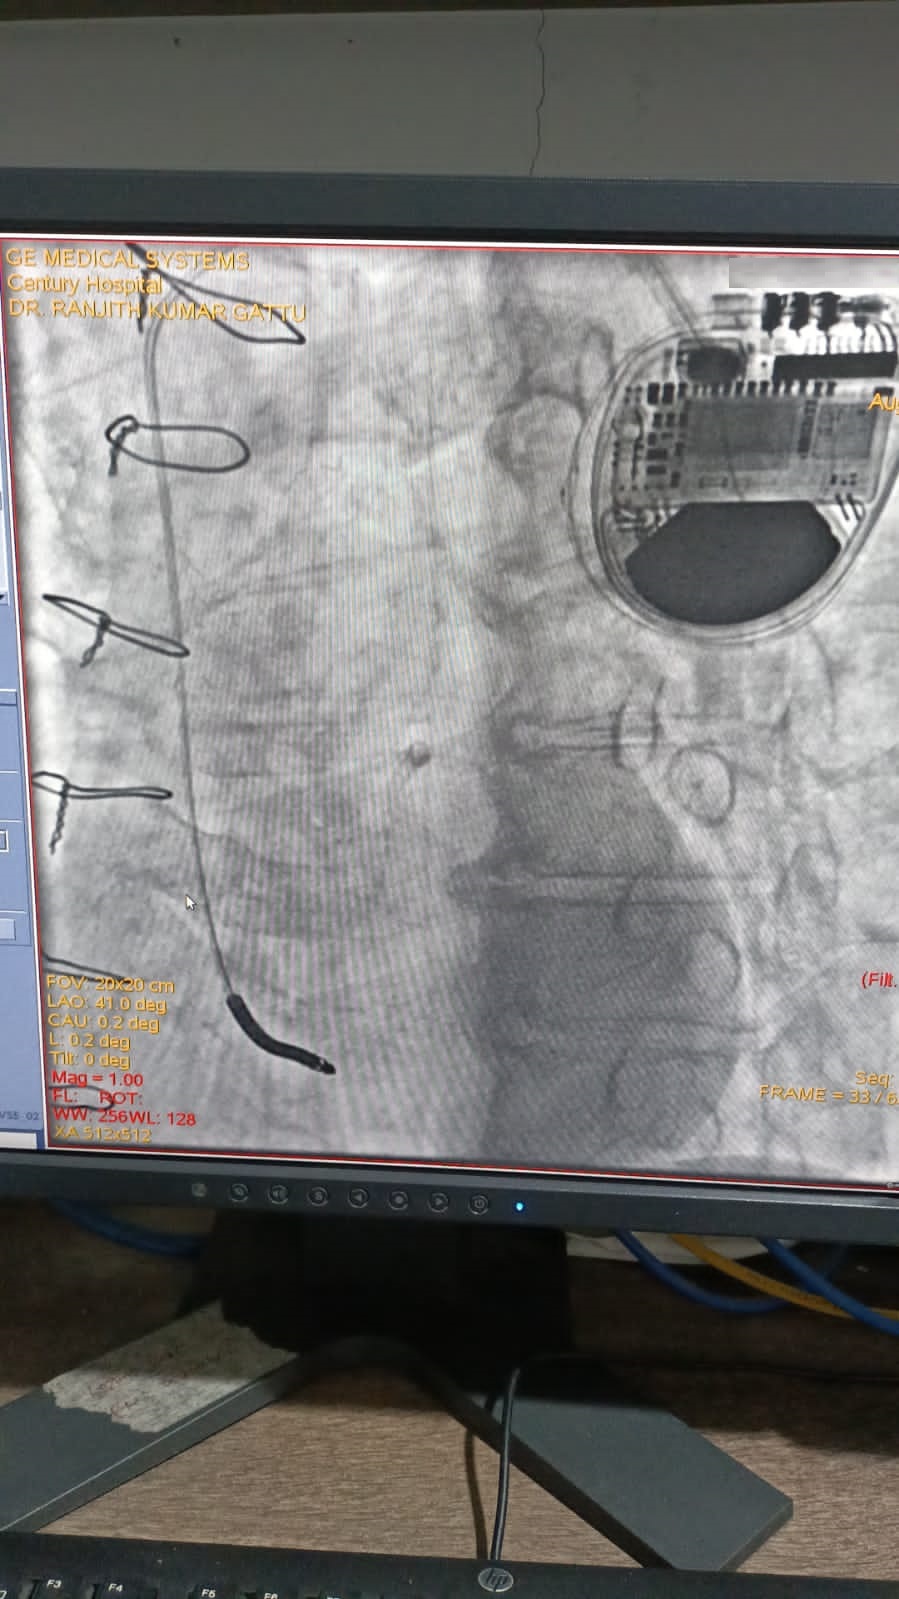

Catheter ablation of arrhythmias

Left Coronary Diseased Artery